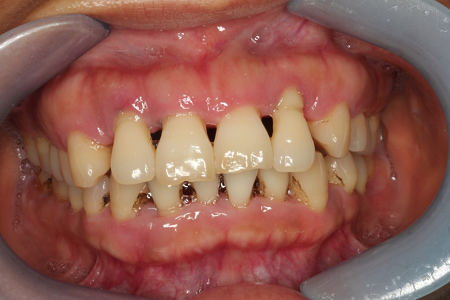

包绕着牙齿的所有组织包括牙周膜、牙槽骨、牙龈就是我们的牙周组织,望文生义,牙周炎就是指着一些组织发生的炎症。因为这些组织发炎了,就会加大牙槽骨的吸收。牙槽骨之于我们的牙齿,就像土壤之于大树,水土流失,大树就没办法继续牢固的屹立于我们的大地,慢慢就会倾斜直至轰然倒塌。

牙周炎最根本的原因在于口腔细菌的影响,而口腔细菌存在于我们每天遗留的食物残渣(可以自行清洁掉),进一步形成软垢(刷牙即可以去除),进一步形成牙石(需要专业设备及专业人士才能清除)。如果我们每天能认真正确的进行口腔卫生的清洁维护,就能很大程度的预防牙周炎。如果我们能在牙周炎最早阶段——牙龈炎时给予正确的预防治疗——洁牙,就能提前把牙周炎的萌芽掐掉,而不至于使您的牙齿保卫战一退再退,最后一败涂地。

如果您没抓住早期预防的时机,等到牙移位,牙松动的时候才来就诊,那就是一个需要定期复诊,终生治疗的疾病。而且我们的常规基础治疗只能是减缓您的牙槽骨吸收速度(减缓程度取决于您的口腔个人卫生维护程度及医从性)。我常给患者打比方:牙周炎就向一辆车载着您的牙齿向悬崖奔去,我们的牙周基础治疗就是给这辆车踩踩刹车,让它跑得不要那么快,可以使您的牙齿多留几年,最理想的情况就是这车长期不动,甚至可以稍微后退一点,但退到原位基本是不太可能的。所以,感到牙齿松动、有异样的患者,请尽快到医院进行检查和治疗。(口腔颌面整形外科 孟丽蕊) |